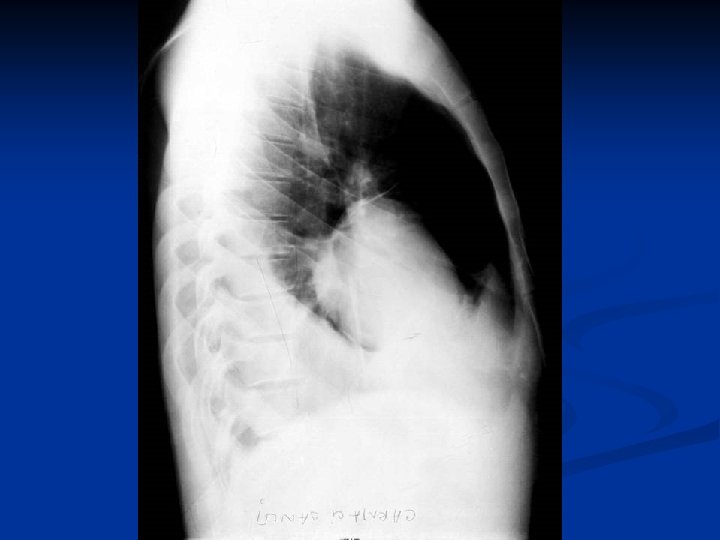

Caracteristici generale n n n Boala parazitara determinata de Taenia echinococcus granulosus. Descrisa inca de pe vremea lui Hipocrat si a lui Galen. Termenul de “chist hidatic” utilizat de Rudolphi in 1908. Localizarea pulmonara este a doua ca frecventa dupa cea hepatica. Boala cu distributie endemica in regiunea mediteraneana, Orientul Mijlociu, Australia, Noua Zeelanda, America de Sud.

Material si Metoda n Studiul de fata analizeaza retrospectiv 162 de cazuri operate in perioada 1999 – 2003.

Concluzii n n n CHP evolueaza mult timp asimptomatic sau cu simptome nespecifice. Diagnosticul

Concluzii n n n CHP evolueaza mult timp asimptomatic sau cu simptome nespecifice. Diagnosticul precoce este deosebit de important avand in vedere evolutia acestei boli. Tratamentul medical antiparazitar (Albendazol) este indicat postoperator. Rezectia pulmonara este o metoda de rezerva in tratamentul chirurgical al CHP. Indicatia operatorie este absoluta, tehnica operatorie alegandu-se in functie de caracteristicile fiecarui caz in parte.